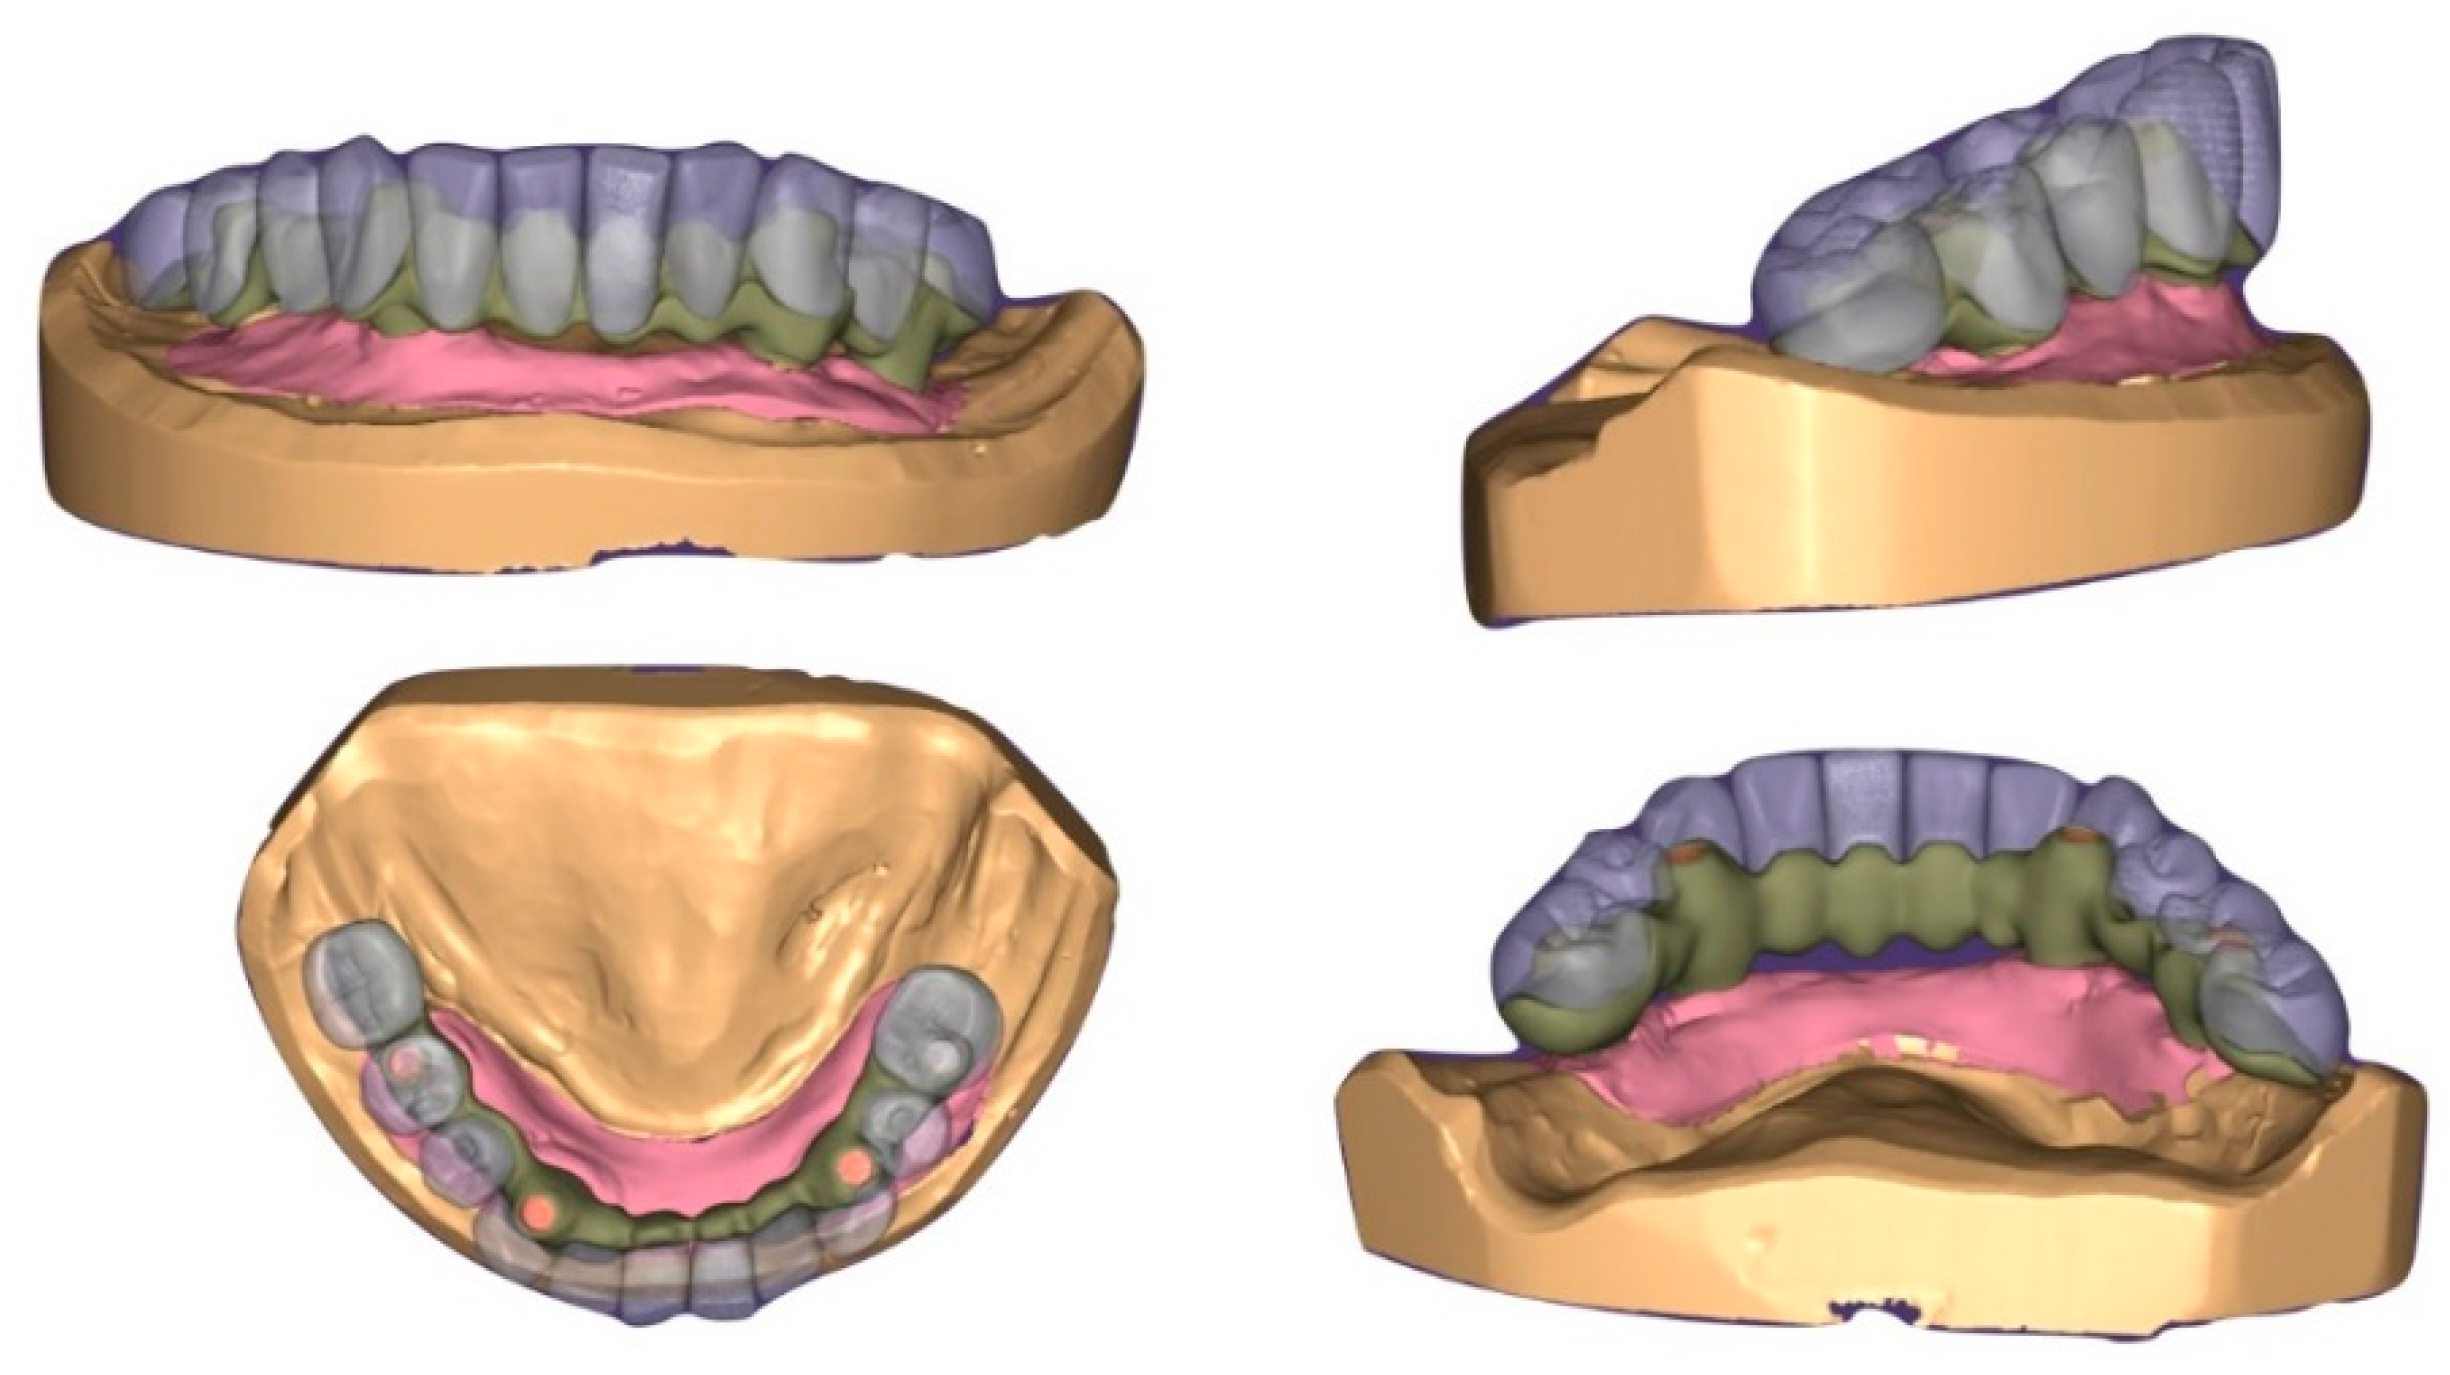

A One-Year, Multicenter, Retrospective Evaluation of Narrow and Low-Profile Abutments Used to Rehabilitate Complete Edentulous Lower Arches: The OT Bridge Concept

- Acampora, R.; Montanari, M.; Scrascia, R.; Ferrari, E.; Pasi, M.; Cervino, G.; Meloni, S.; Lum-bau, A.; Erta, X.; Koshovari, A.; et al. 1-Year Evaluation of OT Bridge Abutments for Immediately Loaded Maxillary Fixed Restorations: A Multicenter Study. Eur. J. Dent. 2020. Ahead of Print. [Google Scholar] [CrossRef]